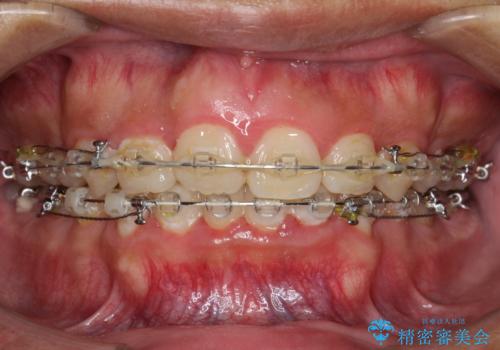

ワイヤー矯正終了時に装置除去と合わせてPMTC

担当医 歯科衛生士